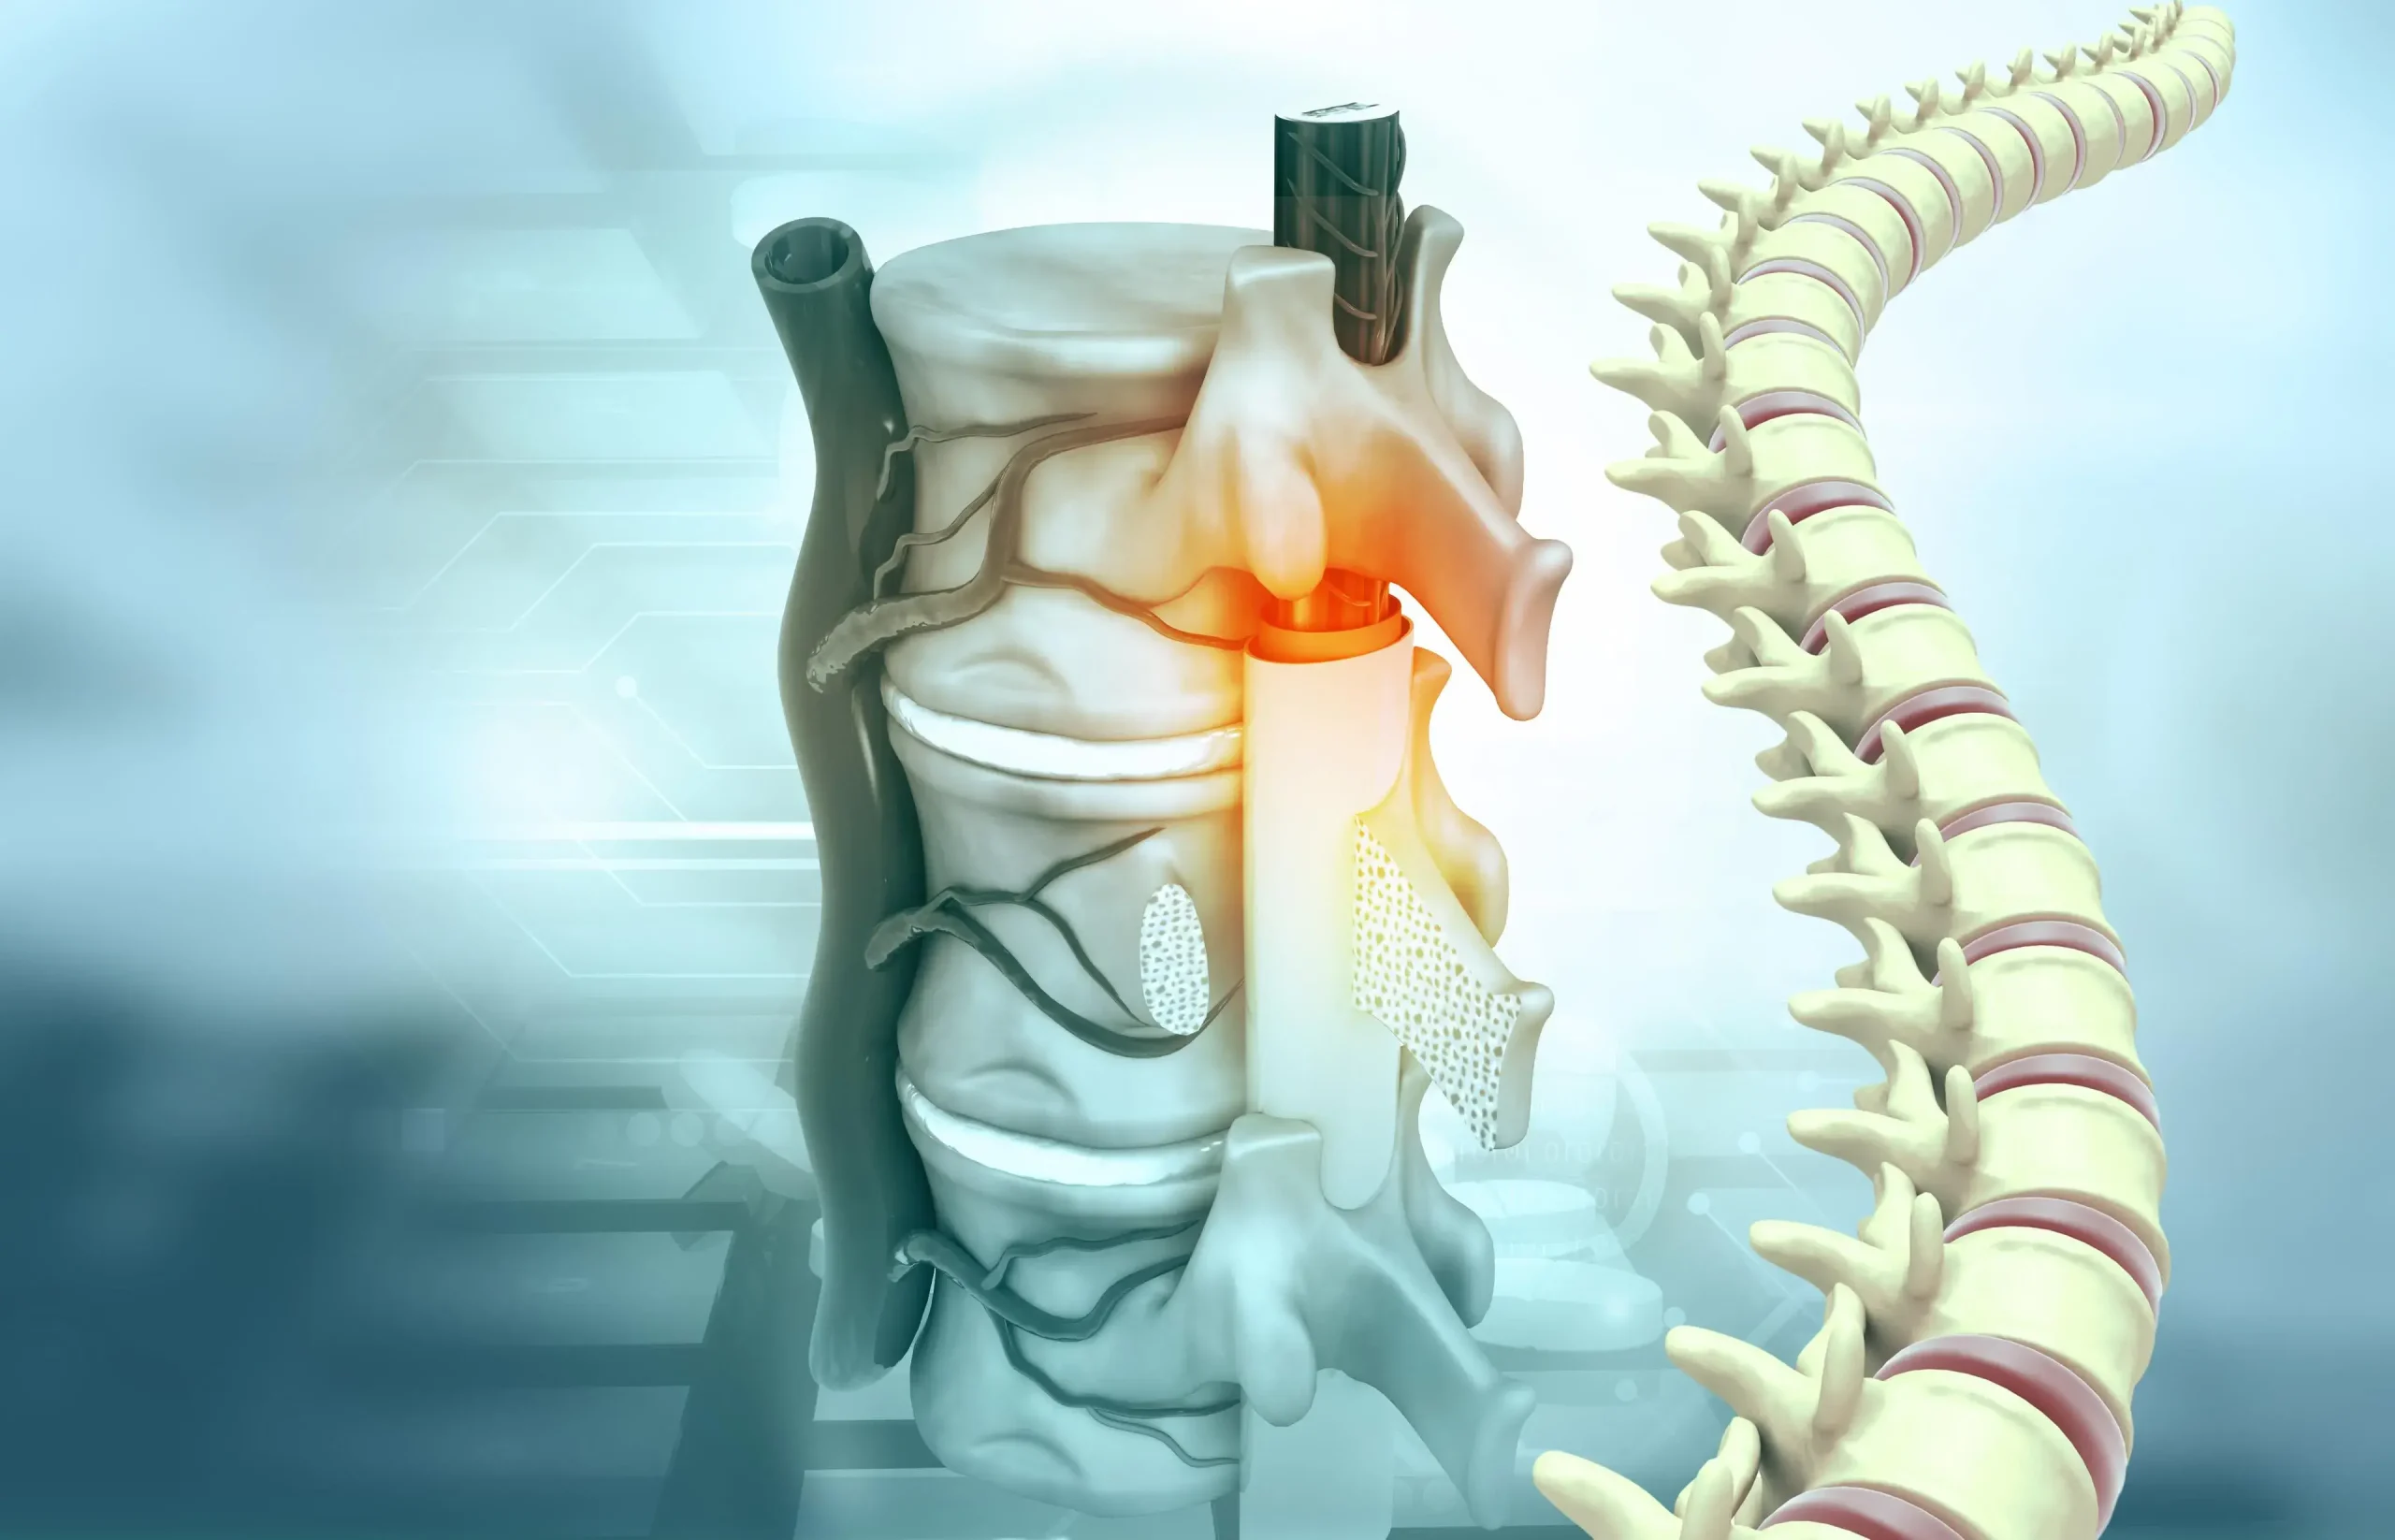

ستون فقرات ساختار پیچیده ای است که از مهره ها، دیسک ها، اعصاب و نخاع تشکیل شده است. از بدن پشتیبانی می کند و امکان انعطاف و حرکت را فراهم می کند. کانال نخاعی که از مرکز مهره ها می گذرد، نخاع را در خود جای داده و از آن محافظت می کند.

- دیسک های بین مهره ای: ساختارهای نرم و بالشتکی بین مهره ها که ضربه را جذب کرده و از اصطکاک استخوان جلوگیری می کند.

هنگامی که تنگی کانال نخاعی رخ می دهد، باریک شدن کانال نخاعی به این ریشه های عصبی و نخاع فشار وارد می کند و علائم مختلفی را ایجاد می کند.

فتق دیسک کمر

هنگامی که مواد نرم داخل دیسک بین مهره ای در اثر بیرون زدگی دیسک کمر به بیرون نشت می کند، می تواند به اعصاب کانال نخاع فشار بیاورد.